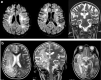

Progressive multifocal leukoencephalopathy (PML) is a fatal demyelinating disease of the central nervous system that is caused by John Cunningham virus (JCV). It occurs almost exclusively in immunosuppressed individuals, for example, patients with AIDS and hematological and lymphoreticular malignancies. In this article, we present a review of the literature and 2 case reports with PML. The first report examines a 15-year-old male (who presented with dedicator of cytokinesis 8 deficiency) who was diagnosed as having PML based on characteristic magnetic resonance imaging (MRI) lesions and a positive PCR for JCV in cerebrospinal fluid. He was transferred for bone marrow transplantation after stabilization with therapy of maraviroc and cidofovir. The second report examines a 6-year-old male who presented with encephalitis and was also diagnosed with AIDS. He was diagnosed with PML and started treatment with cidofovir. His clinical status and MRI findings deteriorated rapidly. In immunosuppressive patients who developed encephalopathy, JCV ought to be considered.